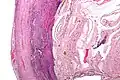

Pathology diagnosis of appendicitis can be made by detecting a neutrophilic infiltrate of the muscularis propria.

Periappendicitis (inflammation of tissues around the appendix) is often found in conjunction with other abdominal pathology.[79]

Micrograph of appendicitis and periappendicitis. H&E stain

Micrograph of appendicitis showing neutrophils in the muscularis propria. H&E stain

Acute suppurative appendicitis with perforation (at right). H&E stain